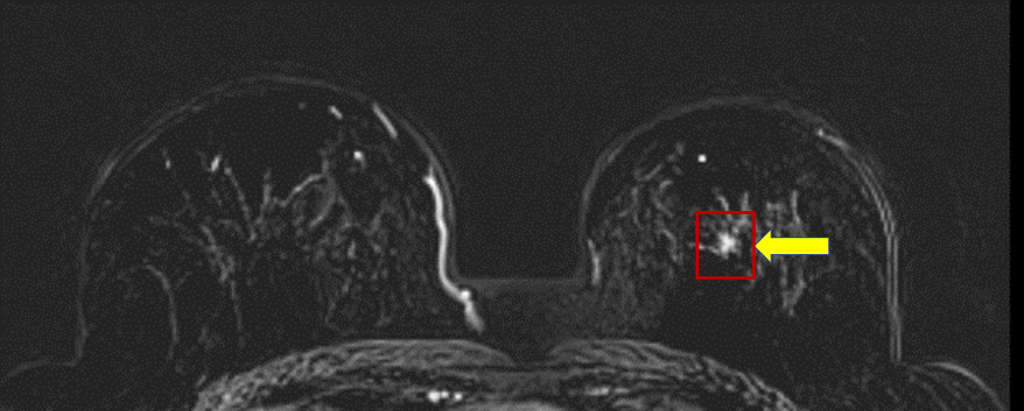

乳癌病灶處。(仁濟醫院提供)

MRI檢查結果卻顯示異常,經判讀為第四等級,也就是屬於高度懷疑惡性腫瘤,醫療團隊隨即建議進行手術切片。患者在充分了解病情後立即同意手術,術後病理檢驗確認為約0.3公分之惡性腫瘤。所幸在癌細胞尚未侵犯周邊組織的原位癌階段,即被發現並切除,成功阻斷後續可能擴散的風險。

協助影像判讀的放射專科梁庭繼教授指出,本次個案在乳房超音波與乳房 X 光攝影未見明顯異常的情況下,仍於 MRI 顯示高度懷疑惡性,最終以手術切片證實約 0.3 公分惡性腫瘤,並在第0期即完整切除,正凸顯 MRI 能在常規檢查仍不明顯時,提前找出「隱形病灶」,為高風險婦女爭取最關鍵的治療時機。